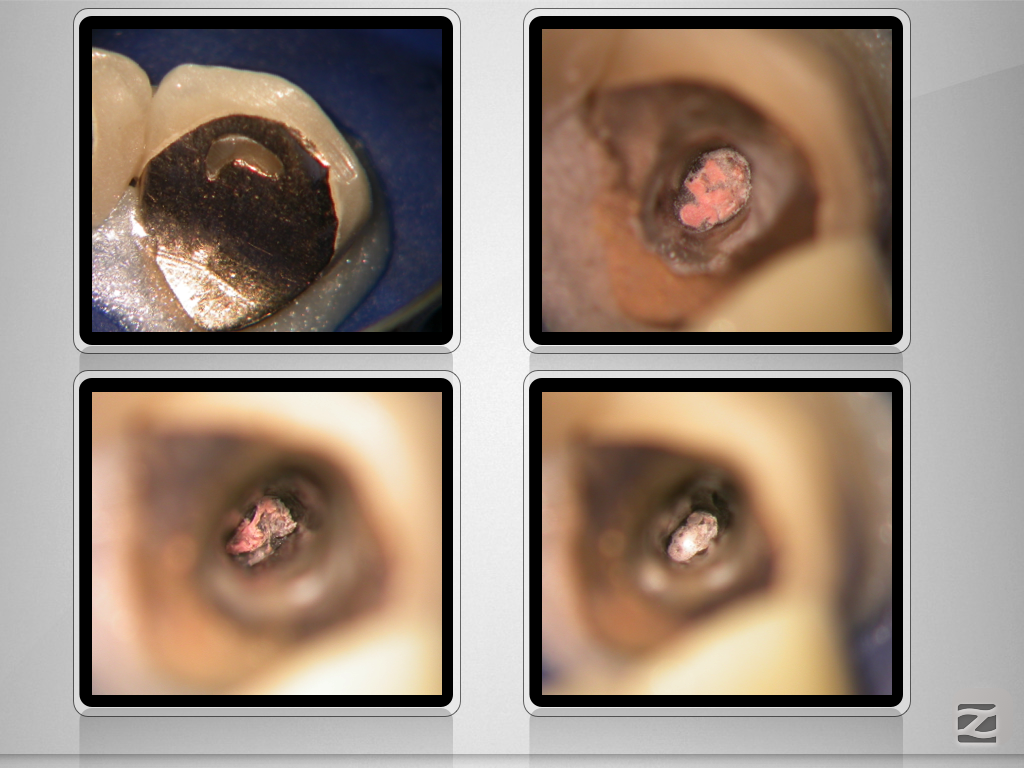

13D.004

Ketac Silver retrograd